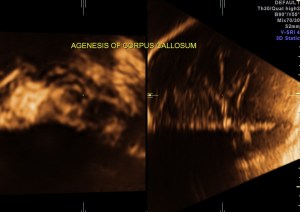

demonstration of both medial and lateral ventricular walls at a level where the single periventricular line is normally demonstrated

A specific diagnosis of agenesis of the corpus callosum has seldom been made before the third trimester, probably because the corpus callosum is not normally formed until 18 to 20 weeks43. Most authors agree that detection of agenesis of the corpus callosum is difficult prenatally, depending as it does on postnatal sonograms or CT or MR scans. In a series of seven fetuses with agenesis of the corpus callosum, Bertino et al35 reported that only three demonstrated a characteristic midline cyst. They described three findings that might lead one to suspect agenesis of the corpus callosum on routine transverse views:

- demonstration of both medial and lateral ventricular walls at a level where the single periventricular line is normally demonstrated, and

- a more parallel course of both ventricular walls than normal.

They suggested that demonstration of these findings on axial views should stimulate additional coronal and sagittal views for evaluation of agenesis of the corpus callosum.

The increased separation of the normal-sized bodies and the enlargement of the atria and occipital horns of the lateral ventricle result in a typical ultrasound image. Upward displacement of the third ventricle is a very specific sign36 but presents only in 40% of fetuses.